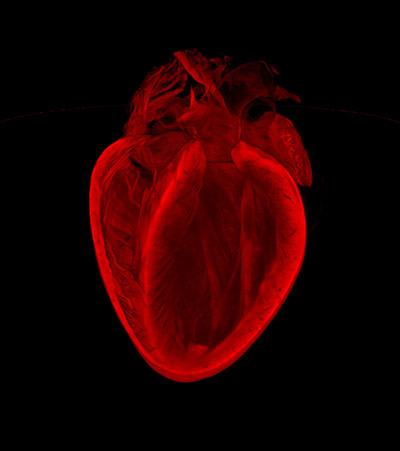

Image of the Year: The Broken Heart by Gillian Gray, Megan Swim and Harris Morrison, University of Edinburgh. This image reveals the 3D structure of an adult mouse heart. It was created using a technique called 'optical projection tomography', which can be used to assess the extent of injury and healing after a heart attack Photograph: Dr Gillian Gray, Megan Swim and Harris Morrison/University of Edinburgh/The British Heart Foundation